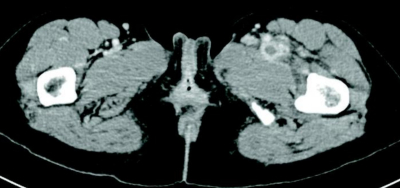

尿所見:蛋白(−)、潜血(−)、白血球3+。検査所見:赤沈 73mm/1時間。血液所見:赤血球 354万、Hb 9.1g/dL、Ht 28%、白血球 8,400(桿状核好中球 5%、分葉核好中球 67%、好酸球 1%、単球 10%、リンパ球 17%)、血小板 36万、PT-INR 1.2(基準 0.9〜1.1)、APTT 27.8秒(基準対照 32.2)、フィブリノゲン 525 mg/dL(基準 186〜355)、Dダイマー 4.1 μg/mL(基準1.0以下)。血液生化学所見:総蛋白7.3g/dL、アルブミン 2.3 g/dL、AST 14 U/L、ALT 11 U/L、LD 144 U/L(基準 120〜245)、尿素窒素 9.1 mg/dL、クレアチニン 0.4 mg/dL、CK 51 U/L(基準 30〜140)。CRP 12 mg/dL。両下肢の写真及び鼠径部の造影CTを別に示す。